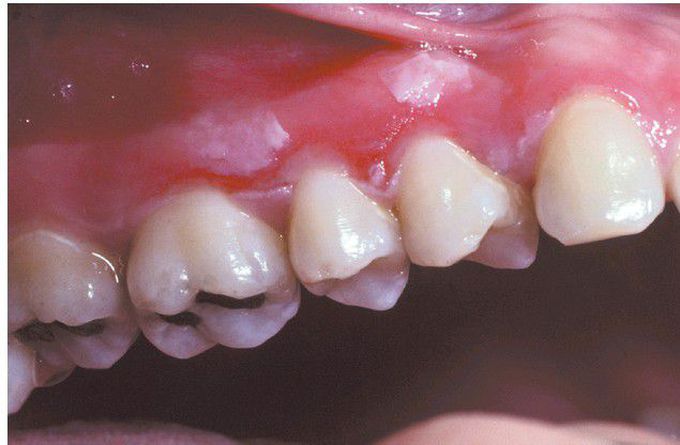

Hydrogen Peroxide Burn.

Extensive epithelial necrosis of the anterior maxillary gingiva secondary to interproximal placement of hydrogen peroxide with cotton swabs.